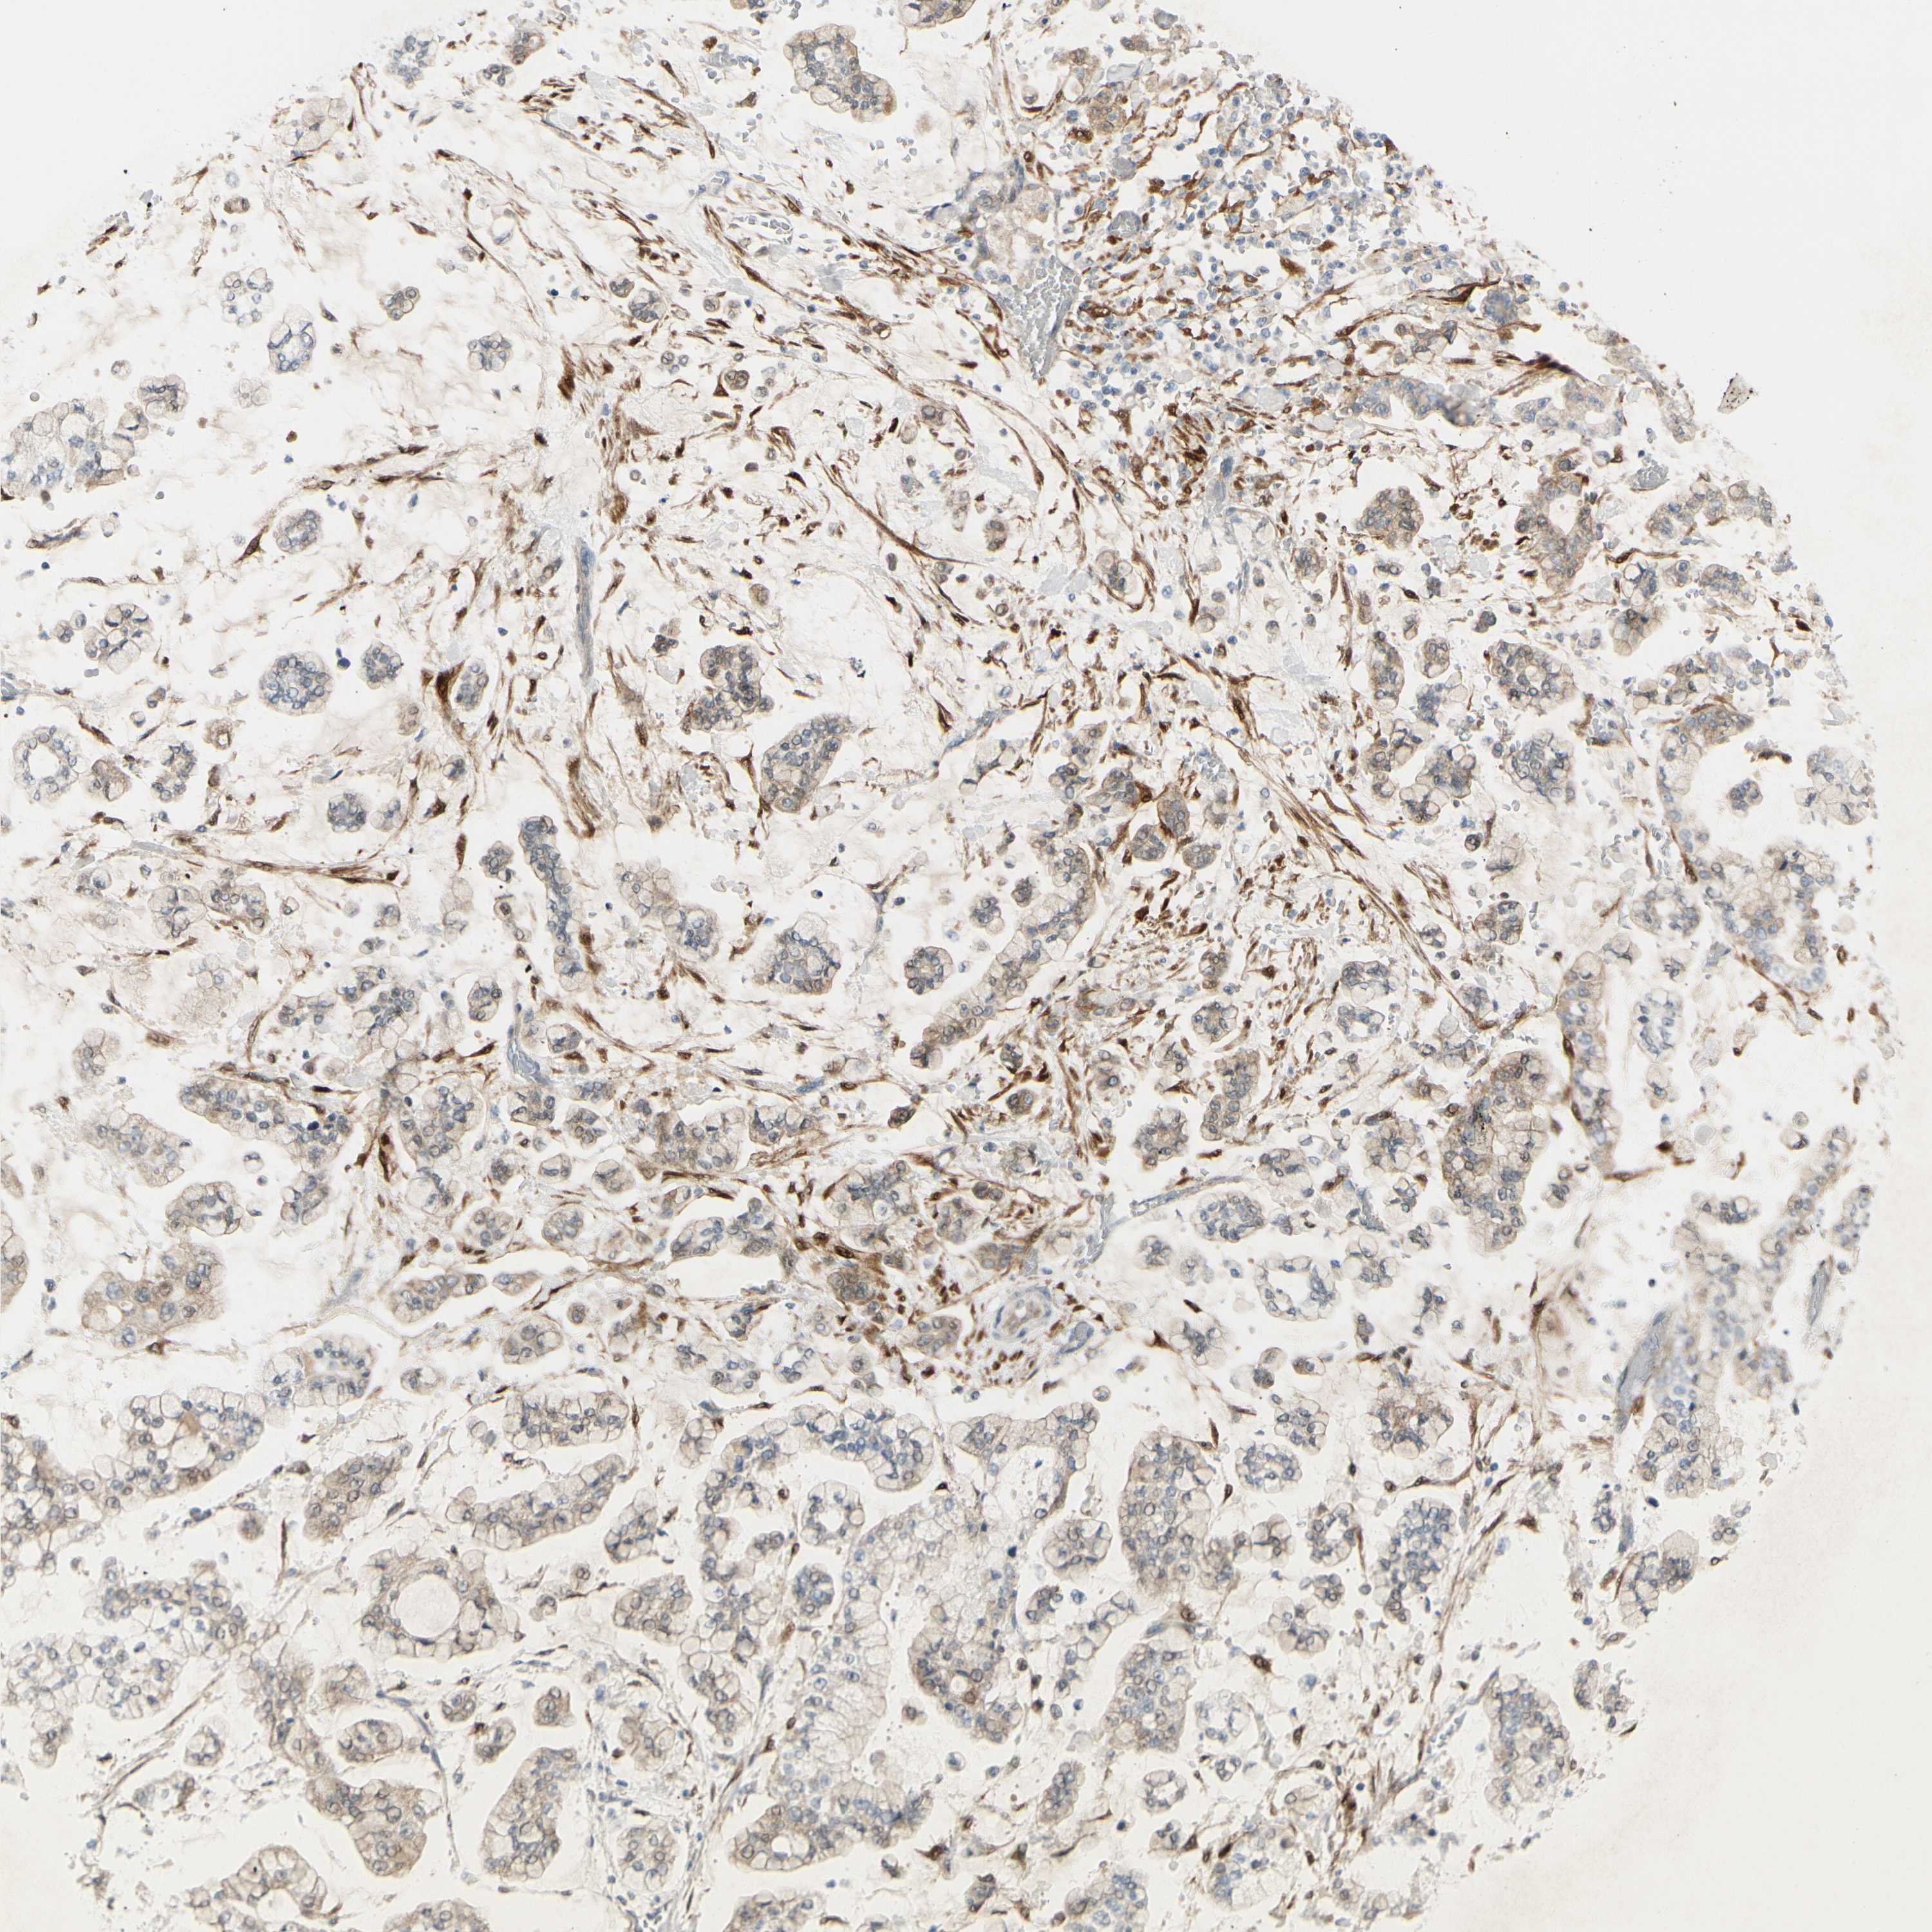

STOMACH CANCER - Protein expressioni

A mouse-over function shows sample information and annotation data. Click on an image to view it in a full screen mode. Samples can be filtered based on level of antibody staining by selecting one or several of the following categories: high, medium, low and not detected. The assay and annotation is described here.

Antibody stainingi

Antibody staining in the annotated cell types in the current human tissue is reported as not detected, low, medium, or high, based on conventional immunohistochemistry profiling in selected tissues. This score is based on the combination of the staining intensity and fraction of stained cells.

Each image is clickable and will lead to virtual microscopy that enables deeper exploration of all samples and also displays staining intensity scores, fraction scores and subcellular localization as well as patient and tissue information for each sample.

Antibody HPA005922

Antibody HPA006028

Antibody CAB008368

Staining

High

Medium

Low

Not detected

Intensity

Strong

Moderate

Weak

Negative

Quantity

>75%

75%-25%

<25%

None

Location

Nuclear

Cytoplasmic/membranous

Cytoplasmic/membranous,nuclear

Adenocarcinoma, NOS

Adenocarcinoma, High grade